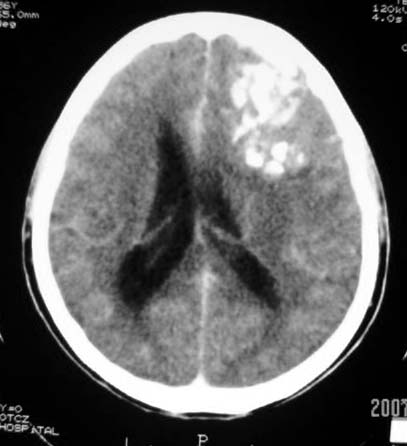

标题: CT7268:左额顶部病变增强片. [打印本页]

标题: CT7268:左额顶部病变增强片.

比较典型的少枝胶质细胞瘤ct表现,局部额骨垂直板有侵蚀变薄。

左额叶病灶内条片状高密度是钙化吗?是的话考虑少支胶质瘤可能大。不然有脑血畸形伴出血可能。

左侧额顶叶有条带状钙化的不规则形占位,增强呈不均匀轻度强化,局部颅骨受侵蚀变薄,典型的少支胶质细胞瘤。

比较典型的少枝胶质细胞瘤ct表现,局部额骨垂直板有侵蚀变薄